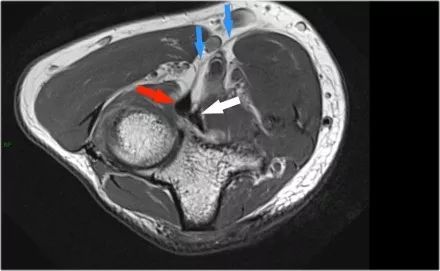

在研究韧带时,尤其是UCL,始终使用轴向图像。如果你看内侧上髁,你会发现后束是一个薄的结构(蓝色箭头)。注意在肘管内的尺神经。

后束形成肘管隧道的地板。支持带覆盖肘管。请注意,前束更厚(白色箭头)。您可以看到前韧带和后韧带之间的区别,即使它们形成一条韧带。走向远端,我们会看到它们合并在一起以附着于崇高的结节。